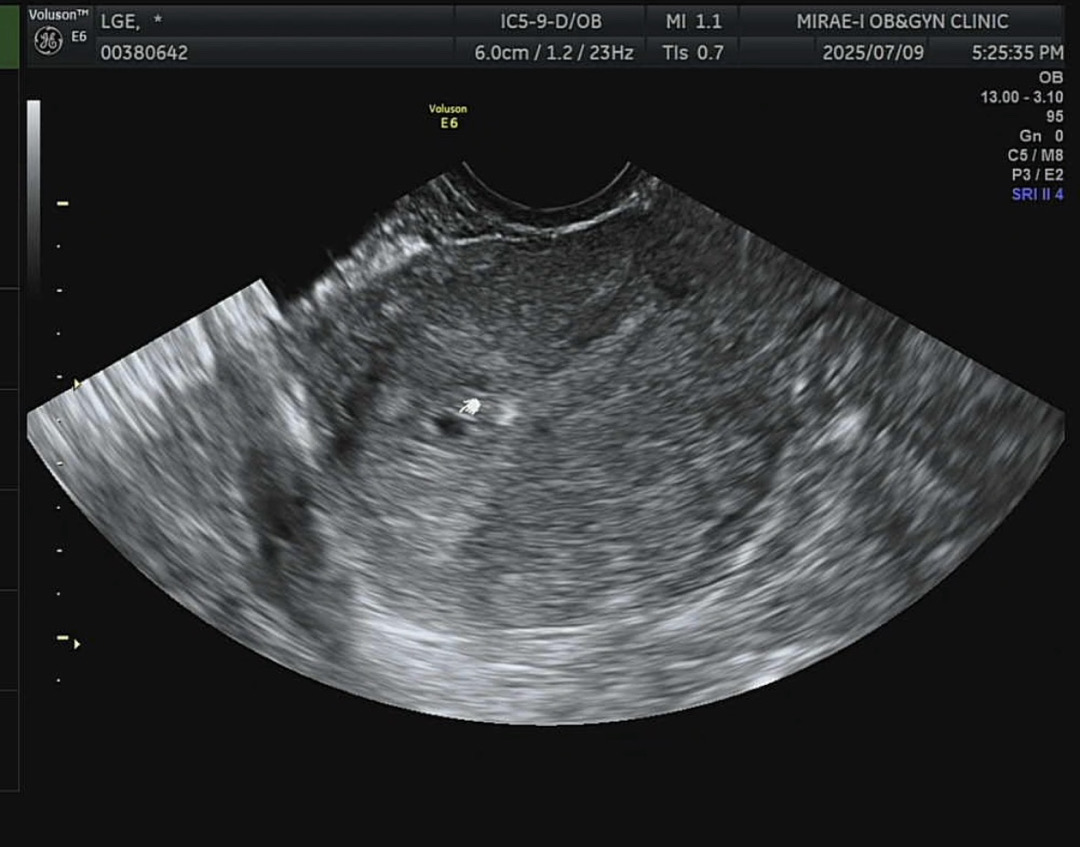

4주 4일 아기집 보고 왔어요!

5주 되는 날은 이번주 토요일인데, 생리 주기가 27일 정도로 짧아서 혹시나 하는 마음으로 오늘 다녀왔어요. 의사선생님이 일찍 온 만큼 오늘은 작은 아기집 보는게 목표라고 하시면서 딱 봤는데 여기있네요!!♥️ 우리집에 찾아온 두번째 아기입니다😊